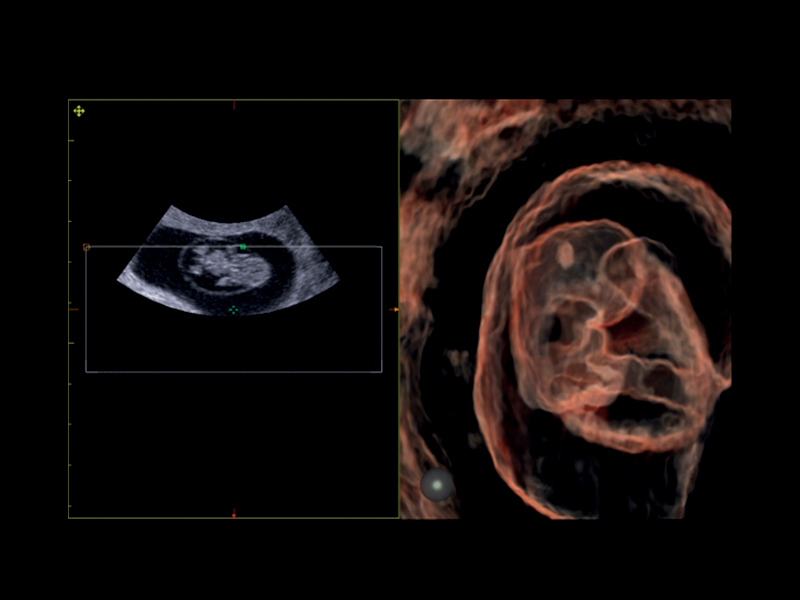

Realistic 3D/4D Depiction of the Fetus

Esaote attaches great value to the quality of its 3D/4D imaging in order to provide very detailed picture of the baby’s features, depending on the stage of fetal development. Its environment is provided by different modalities, based on how the volume can be processed and rendered.

Esaote XLight technology, with its realistic diffusion effects and shadows, emphasizes the anatomical details of the fetus in baby face scanning; XGlass creates a transparency effect; bone rendering is ideal to study the baby’s spine; TSI (Thick Slice Imaging) is suitable for well-defined and confined structures, such as the corpus callosum; finally, XSTIC accurately evaluates the fetal heart.

Clinical Images